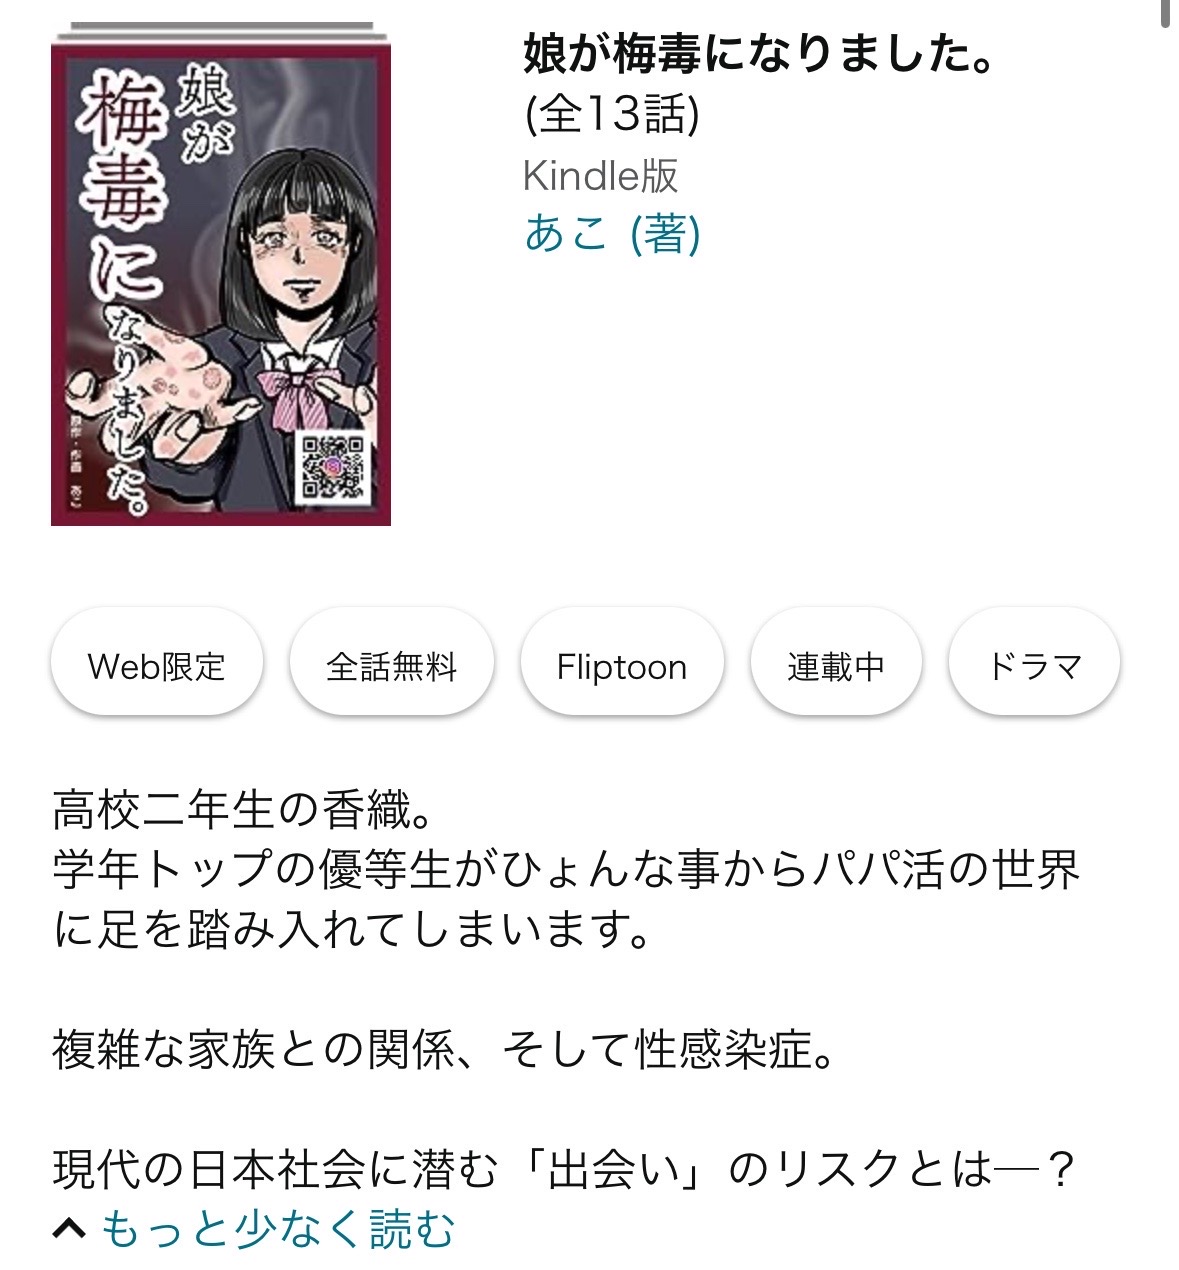

「娘が梅毒になりました」Kindle版、現在無料で公開中です。

ブログには無い作品解説があったりしますので

もし宜しければチェックしてみて下さいませ。